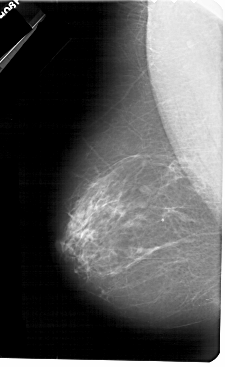

A_1328_1.RIGHT_MLO

RIGHT_MLO LINES 5491 PIXELS_PER_LINE 3046 BITS_PER_PIXEL 12 RESOLUTION 43.5 OVERLAY